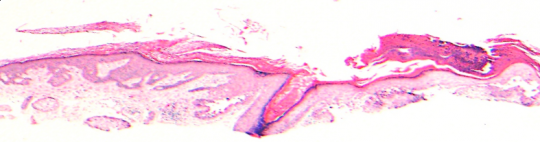

VA35: Left Temple, Actinic Keratosis, Hypertrophic

- White arrows indicate return to dermal collagen texture and reflectivity

VA35: Left Temple, Adjacent, Normal